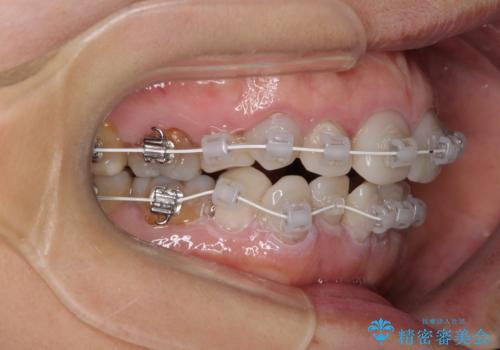

- 小さいころからの歯の変色と矯正治療の後戻りを気にして来院された患者様です。

気になる変色歯を仮歯に変え、その後歯列不正を矯正治療で改善し、最後にオールセラミッククラウンにて補綴治療することとしました。